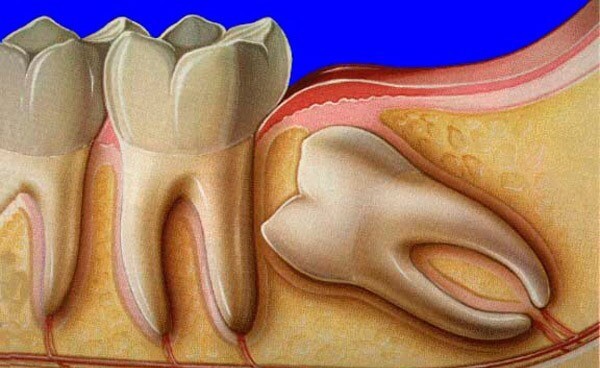

В зубном ряду третьи моляры занимают самое крайнее положение и замыкают зубную дугу. Отсутствие при визуальном осмотре еще не говорит, что у человека их нет: иногда восьмерки находятся в толще десны. Такая патология называется ретенцией, как она выглядит смотрите на фотографии.

Проблемы с «восьмерками» начинаются еще тогда, когда они не успели вырасти: на этапе их прорезывания. Любое отклонение зуба от вертикальной оси является патологией, которая называется дистопией. В зависимости от направления, в котором отклоняется зуб мудрости, выделяют несколько ее типов:

так растут зубы мудрости при дистопии

Помимо отклонений в росте, существуют и другие. К примеру, мудрый зуб может совсем не прорезаться через десну или же прорезаться частично, в этом случае он называется ретинированным или полуретинированным. Иногда моляр занимает нормальное положение (вертикальное погружение) или же лежит на боку (горизонтальное положение).